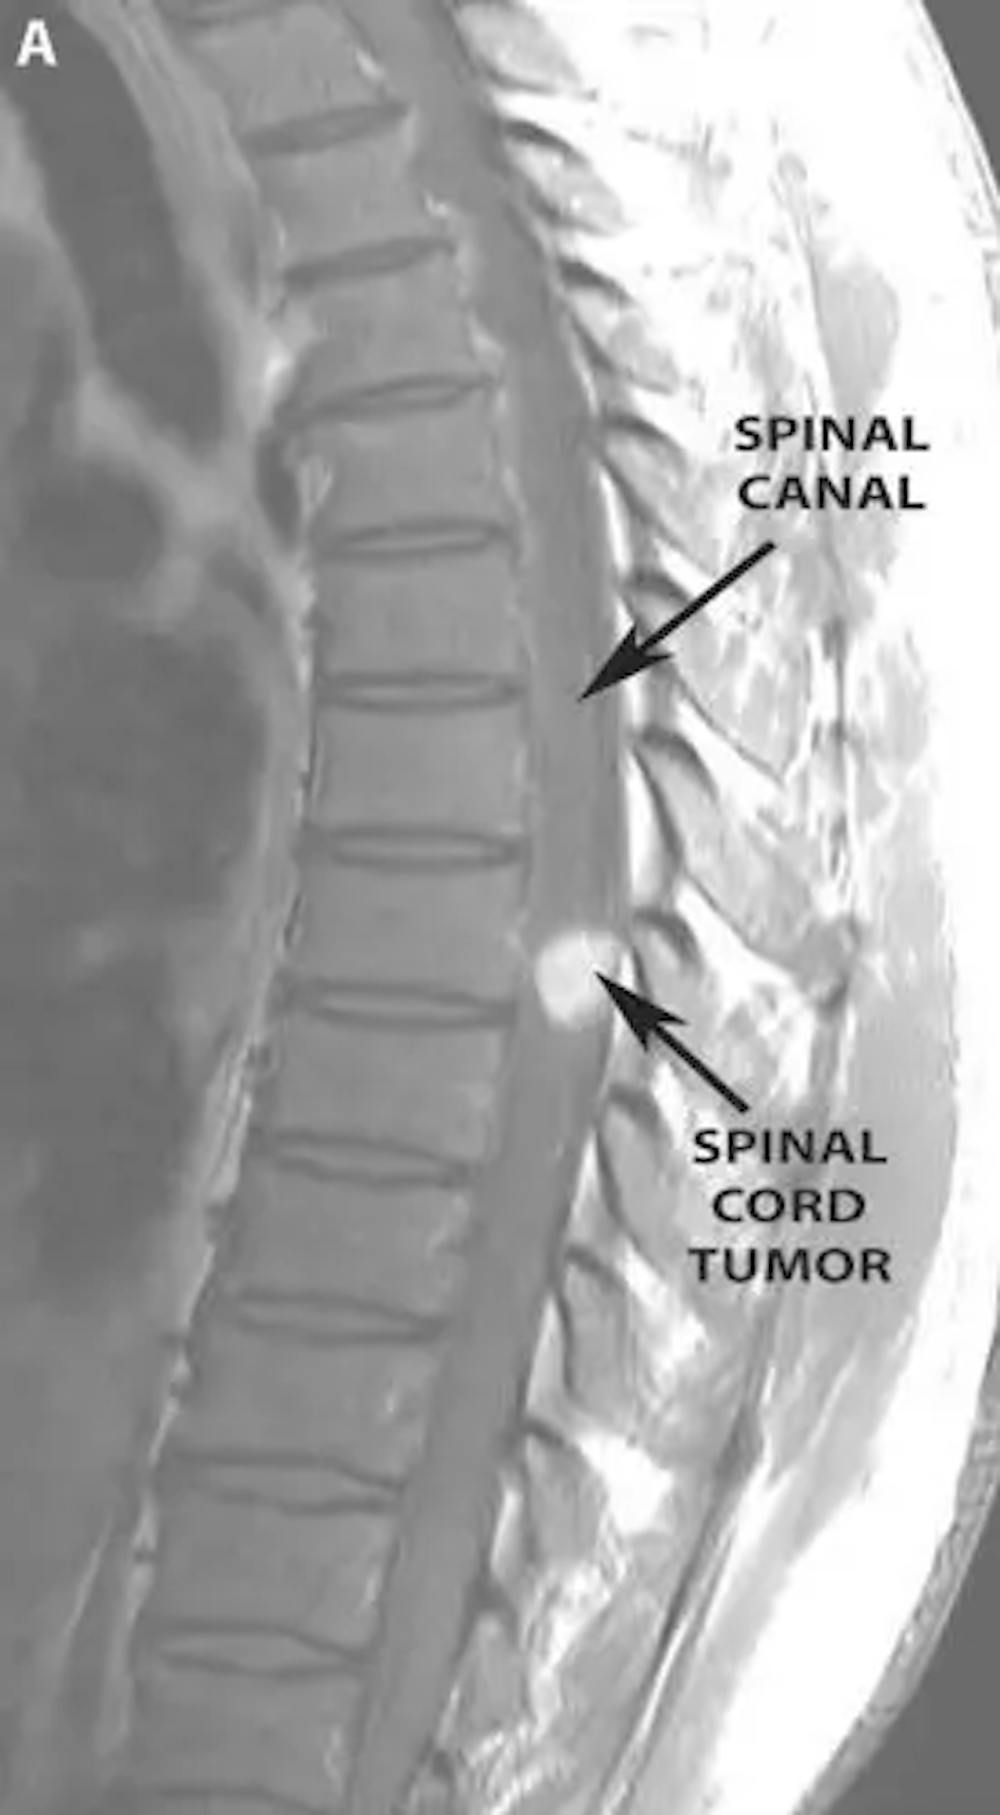

A) Pre-operative MRI with contrast of the thoracic spine demonstrating an enhancing tumor in the spinal canal compressing the spinal cord.